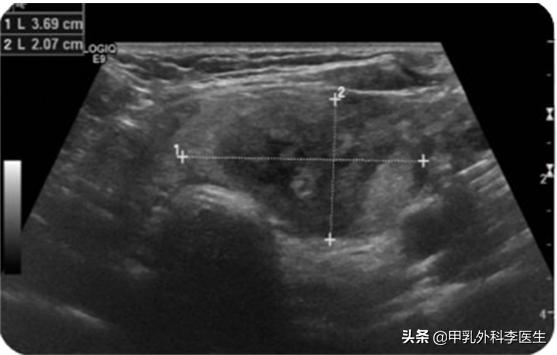

术后3个月肿块体积:3.7*2.1cm